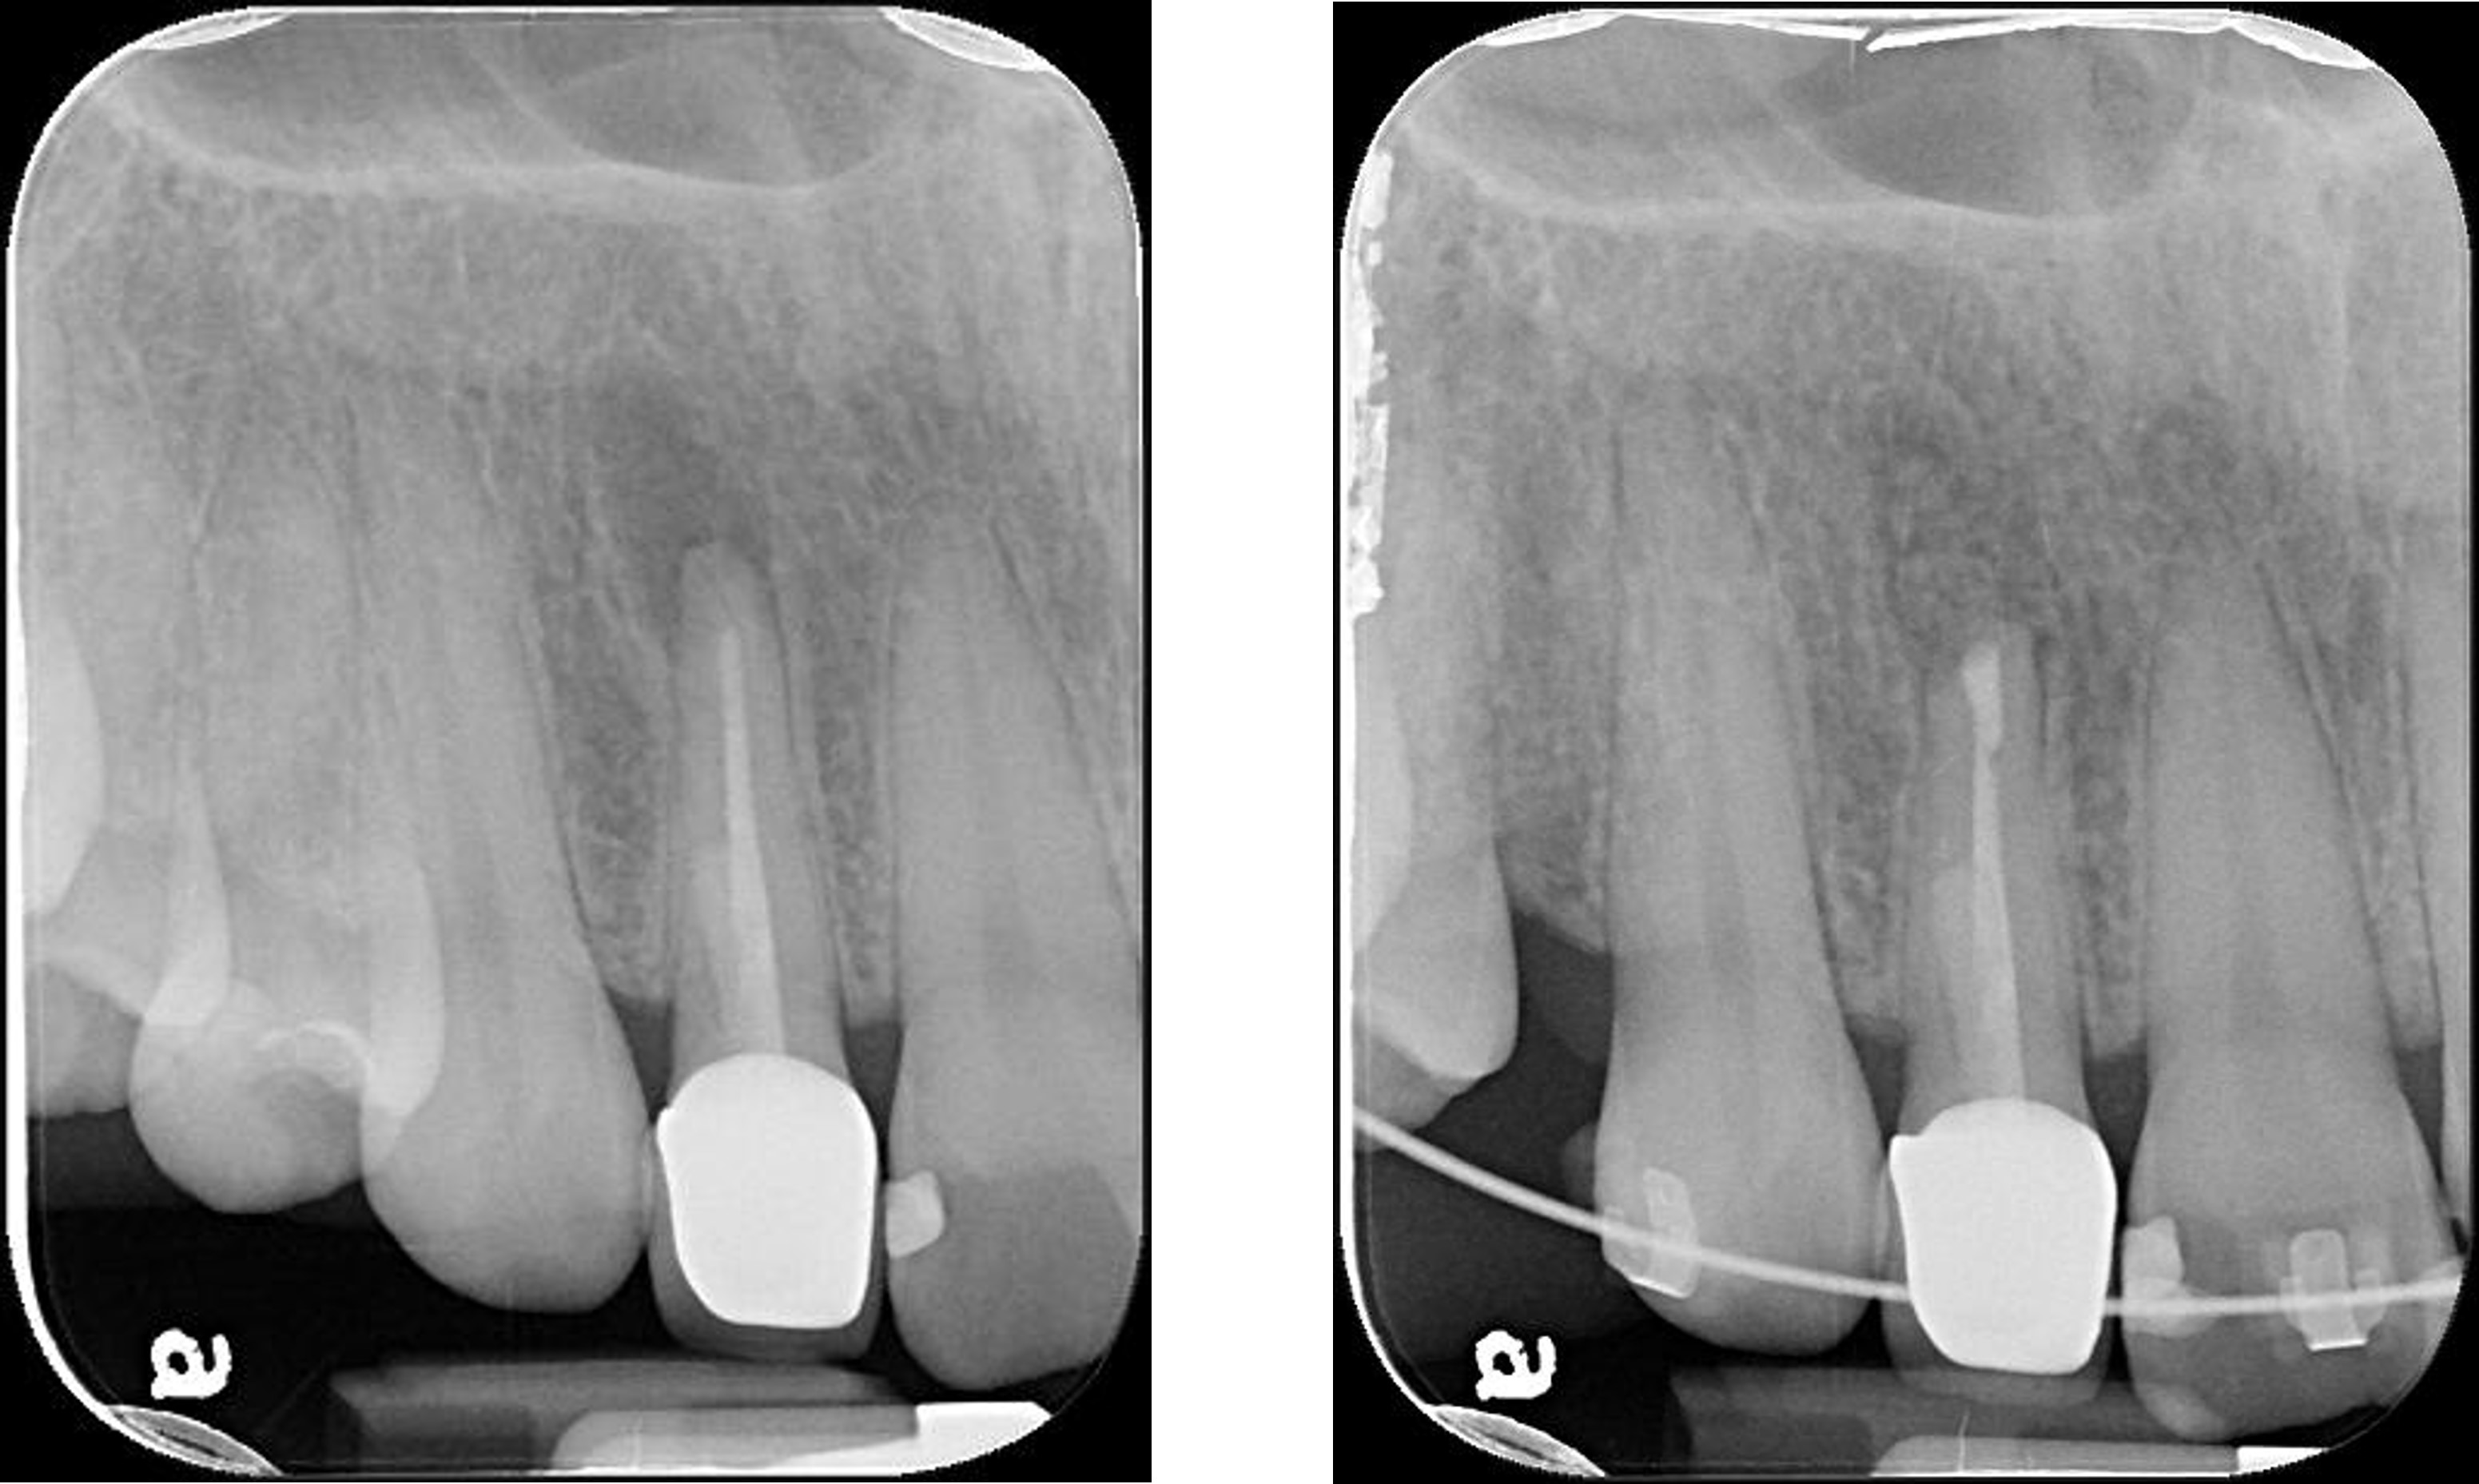

1年後根尖片追蹤

術前、術後比較